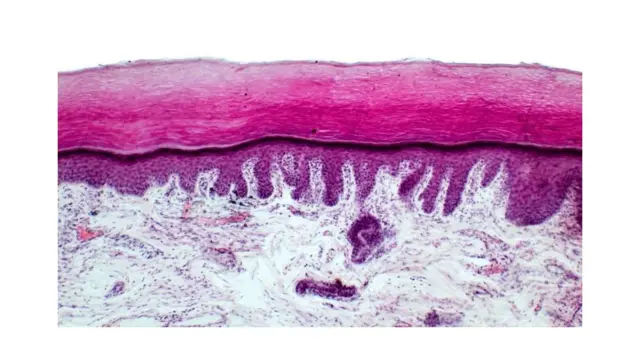

Mais c'est l'environnement qui a tendance à faire le plus de dégâts. Si les rayons ultraviolets B (UVB) peuvent endommager l'ADN - provoquant des brûlures, des mutations et des cancers de la peau - 95 % du total des rayons ultraviolets atteignant la surface de la terre sont des ultraviolets A (UVA).Cette partie du rayonnement solaire a une longueur d'onde plus grande, ce qui lui permet de pénétrer profondément dans le derme, où elle décompose le collagène et stimule les cellules à produire de la mélanine.Au niveau microscopique, la peau photovieillie, c'est-à-dire la peau qui a vieilli sous l'effet du soleil, est plus épaisse et présente des enchevêtrements de fibres d'élastine et de collagène difformes.